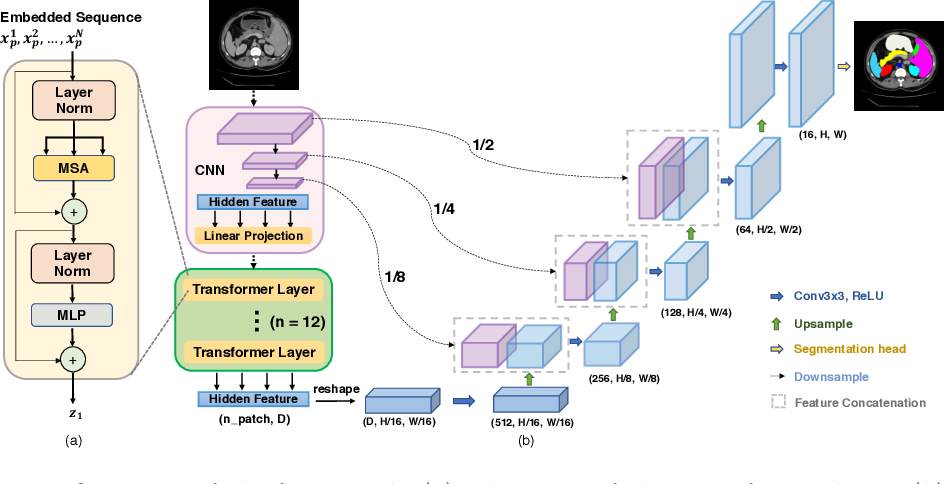

SETR

Paper: 《Rethinking Semantic Segmentation from a Sequence-to-Sequence Perspective with Transformers》

Accepted by CVPR 2021.

文章解读:https://zhuanlan.zhihu.com/p/348418189

SETR 记得没错的话应该是当时最早将 ViT 引入语义分割框架的代表型工作之一。